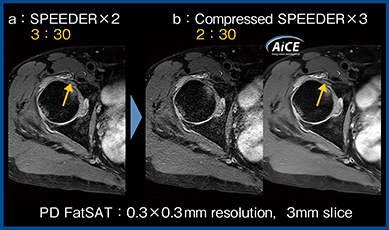

Compressed SPEEDERは2Dのfast spin echo(FSE)法に適用可能であることから,2D撮像を多用する整形領域MRIのトータルの撮像時間の短縮に貢献する。また,撮像時間が短縮する分,より高分解能条件に設定することも可能となる。図4のように,低SNRの画像にCompressed SPEEDERを適用するとノイズが増加するケースもあるが(b左),さらにAiCEを適用することで,SPEEDERを適用した画像(a)よりも撮像時間を短縮しつつSNRも担保され,関節唇損傷(↑)がより明瞭に描出されている(b右)。

図4 Compressed SPEEDERとAiCEの併用による

脂肪抑制PD強調画像(関節唇損傷)